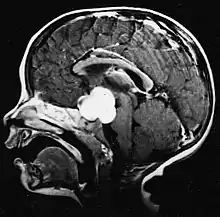

Stereotactic MRI brain scan showing a recurrent postoperative brain stem cystic pilocytic astrocytoma.

Sagittal T1-weighted MRI showing a well-circumscribed hypointense mass in the tectum (presumably a tectal plate glioma). These lesions are a distinct subset of pilocytic astrocytoma which present with hydrocephalus typically in 6 to 10 year-olds and are rarely progressive lesions. When imaging is characteristic, a biopsy is usually not performed because of the risks to adjacent structures, often shunting to relieve intracranial pressure is the only treatment required.

T1-weighted coronal MRI image postcontrast showing heterogeneous contrast enhancement within the presumed tectal plate glioma